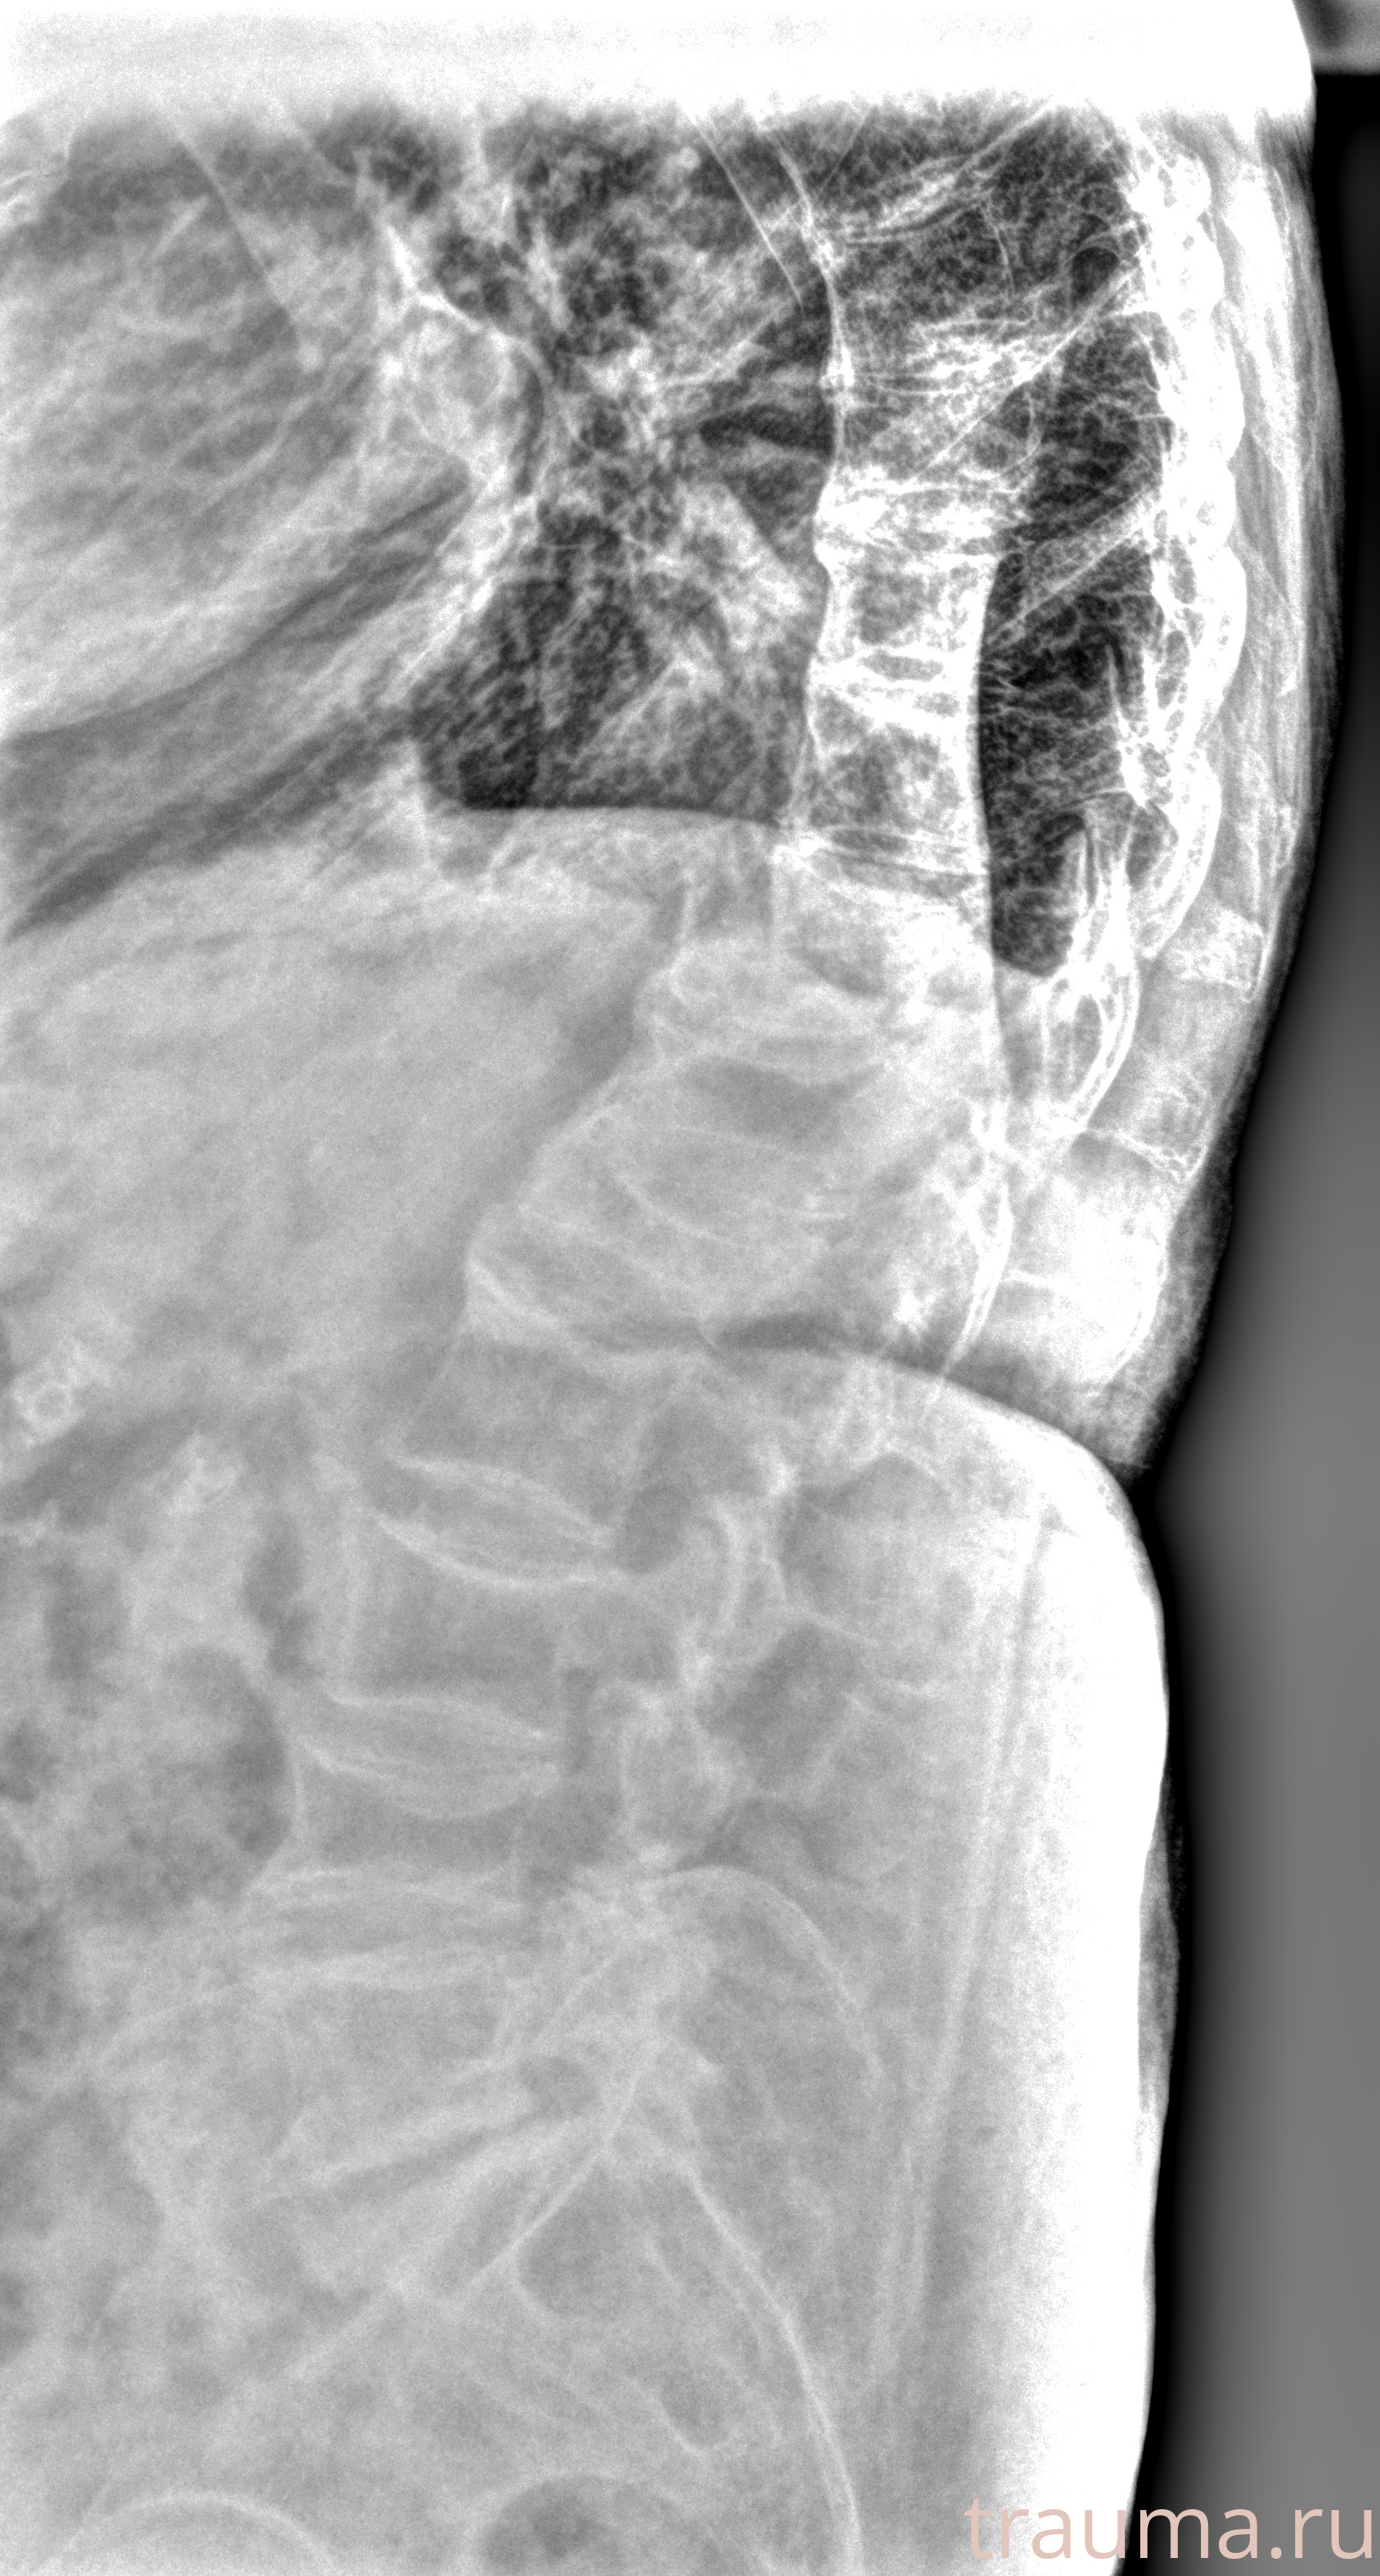

Рентген на дому: по вашему адресу приезжает врач-рентгенолог, травматолог-ортопед с мобильным рентгеновским аппаратом, проводит диагностику травмы или заболевания, делает необходимые рентгенограммы, дает рекомендации по дальнейшему лечению. Получить качественные снимки в домашних условиях возможно благодаря уникальной методике, разработанной МосРентген Центром для института  Склифосовского

при переломе шейки бедра и пневмонии от компании МосРентген Центр - партнера Института имени Склифосовского